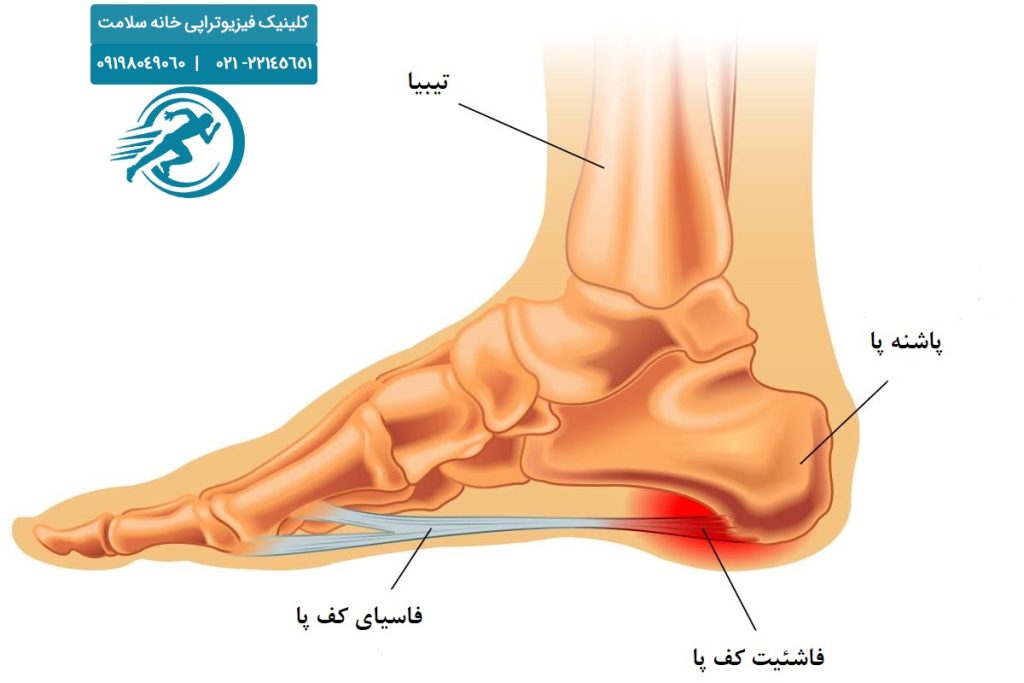

درمان خار پاشنه در منزل

خار پاشنه بین خانمها و آقایان به عنوان یکی از بیماریهای شایع در پا شناخته شده است، اما تا زمانیکه فرد درد شدیدی در پاشنه پا احساس نکن...